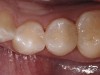

Figure 19  Immediate postoperative view of the completed restorations, after which the rubber dam was removed for verification of the occlusion.

Figure 19

Figure 20  Postoperative view of the completed posterior restorations.

Figure 20